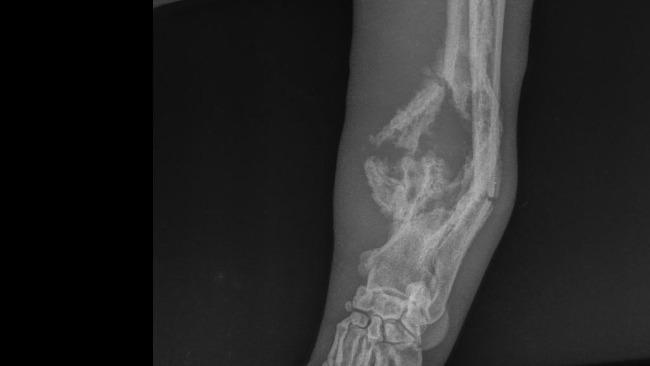

Babsi gdy trafiła do przechowalni miesiąc temu miała wydawało się zdrowe cztery łapy. Kulała jednak. Po miesiącu jej przednia łapa uległa nienaturalnemu wygięciu. Trafiła do kliniki weterynaryjnej. Po wykonanych zdjęciach RTG lekarze podejrzewali agresywny nowotwór kości bądź złamanie. Wiadomo było, że powrót suni do schroniska jest niemożliwy.

Zdjęcia RTG po przyjeździe Babsi do nas skonsultowaliśmy z 3 ortopedami. Niestety wszyscy są zgodni co do tego, że łapa wygląda źle i być może możemy mieć do czynienia z agresywnym nowotworem kości.

Po wszelkich badaniach, Babsi została zakwalifikowana do operacji amputacji. Po wykonanej operacji materiał trafi do badania histopatologicznego który da nam już ostateczną diagnozę.